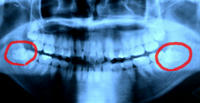

今行ってる臨床先でひょんな事から自分の口周りのレントゲン写真を撮って貰う事に。

今まで小さいの(通称デンタル)を撮った事はあっても、大きいの(通称パントモ)は撮った事がなかった。

↓フレアさんのお口周りのレントゲン~♪

まぁものの見事に親知らずがおりましたとさ。

下の歯がね。どー頑張っても正常に生えないって言う。。。

あっはーvこれ痛み出したらメスで切開してゴリゴリ分解して取り出さないとだよーvv

痛まない事を切に祈る。。。(凹)